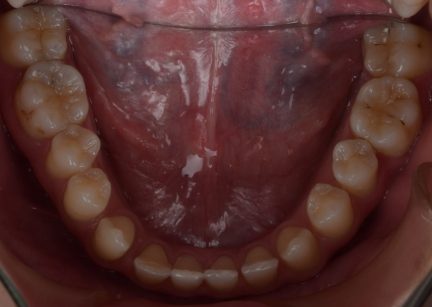

Classe I, morsure bord à bord, espacement, diastème

Facettes

Avec l'aimable autorisation du Dr F. Wang, 2021

État initial